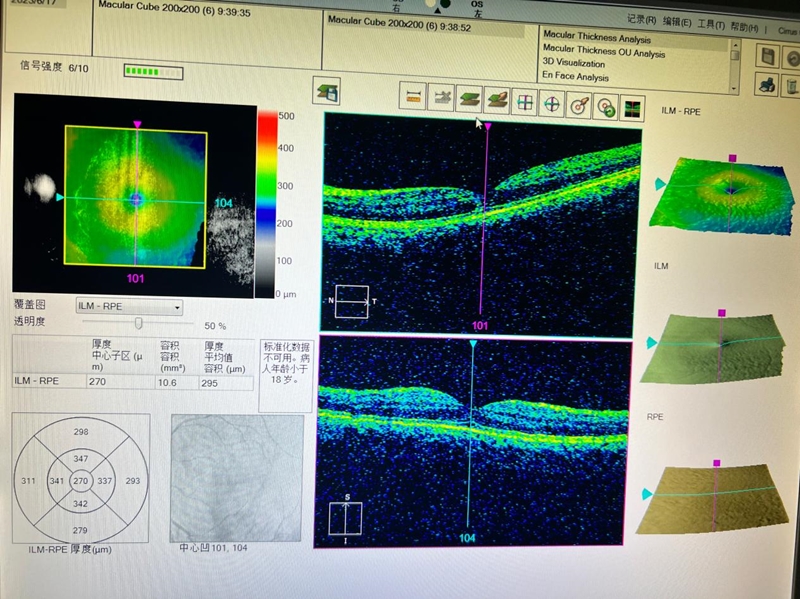

无独有偶,近日,又有一位年仅14岁的初中生小吴在家中玩耍时被激光笔照射左眼,造成左眼眼底黄斑中心瘢痕,视力严重下降。类似激光损伤眼睛事件层出不穷,令人触目惊心。